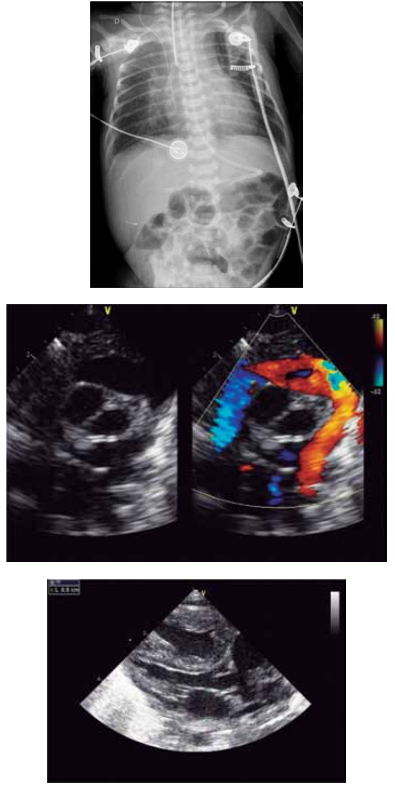

Paciente de 1 mês de idade foi admitido em Unidade de

Terapia Intensiva, acompanhada de cuidadora de abrigo,

devido à piora da cianose. Mãe drogadita perdeu guarda

dos 6 filhos. A saturação na Unidade manteve-se estável,

ao redor de 84%, sem insuficiência cardíaca congestiva,

em uso de propranolol; foi acompanhado no ambulatório

até os 2 anos de idade e realizada intervenção cirúrgica

cardíaca. Com base nos seguintes exames complementares, quais seriam, sucessivamente, a cardiopatia congênita provável, a cirurgia realizada aos 2 anos de idade

e a cirurgia atual para a qual foi convocada?

(Arquivo pessoal; imagens usadas com autorização)